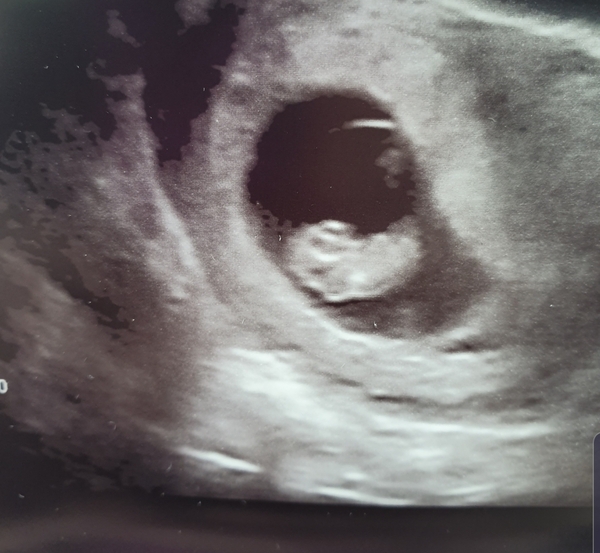

I had my second scan today... photo attached. I am so happy! Baby was right there little heartbeat fluttering away 🥰 I feel so much better now, like I can relax a little. Although just looks like a blob right now as I'm only 7+1 according to the sonographer, by my calculations I'm 7+2 so we shall see what they say at my 12 week scan!